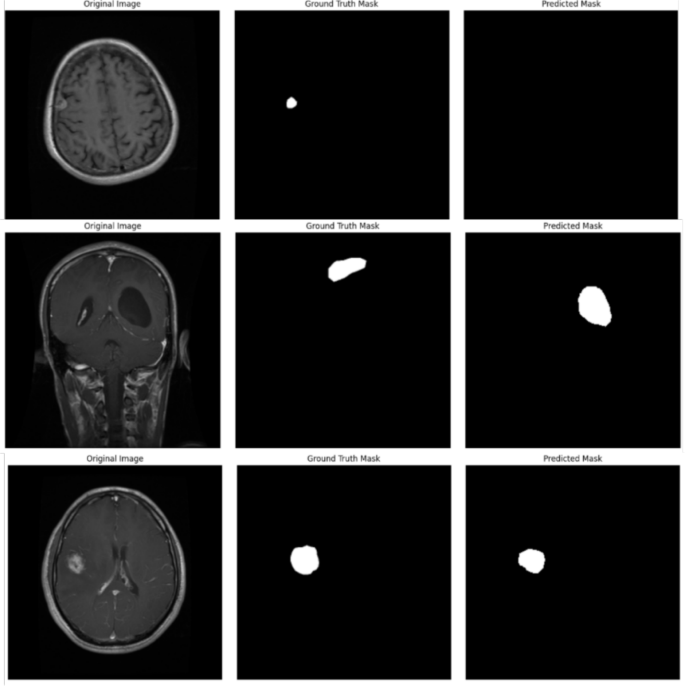

Comparison of EfficientNet variants

Table 4 summarizes the segmentation performance of the EfficientNet variants (B0-B7) combined with the Multiscale Attention U-Net. EfficientNetB4 was the most successful backbone for our segmentation framework, achieving the highest Dice Coefficient 0.9339 and IoU 0.8795 out of all the variants. EfficientNetB4 outperformed other models in correctly recognizing tumor regions by exhibiting a balanced trade-off between feature extraction capability and parameter efficiency. These results were further supported by the segmentation outputs’ visual quality. As shown in Fig.6, the predicted masks from EfficientNetB4 closely resembled the ground truth masks, accurately capturing tumor boundaries. In contrast, other variants, such as EfficientNetB3 and EfficientNetB7, exhibited minor inconsistencies, including over-segmentation and under-segmentation, particularly in cases with complex tumor shapes. These differences highlight the importance of selecting an optimal backbone that balances model complexity and generalization ability. Interestingly, while deeper variants such as EfficientNetB6 achieved comparable performance (Dice Coefficient: 0.9327, IoU: 0.8778), they required significantly more computational resources. This makes EfficientNetB4, a more practical choice for achieving high performance with lower computational overhead.

Visualization of misclassified images

To gain insights into the limitations of the proposed EfficientNetB4 with Multiscale Attention U-Net, visualizations of misclassified cases were analyzed. Figure 8 presents examples where the model produced false positives or false negatives.

The misclassifications were primarily observed in cases with low contrast between the tumor and surrounding tissues, as well as in complex tumor shapes with irregular boundaries. These challenges resulted in false positives where non-tumor regions were segmented as tumor and false negatives where actual tumor regions were missed.

This analysis highlights the need for enhanced boundary delineation techniques and improved feature extraction methods to minimize false detections and enhance the overall segmentation performance.